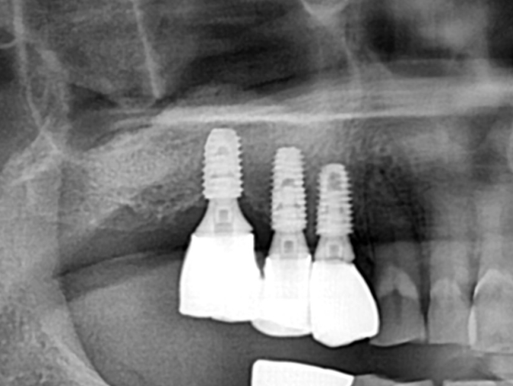

타원 실패 임플란트 재 시술 증례.

After

잇몸 뼈가 많이 소실된 상태이므로 임플란트 재수술은 보통 더 어려울 수 밖에 없습니다.

위 케이스에서는 상악동 거상술을 측방 접근법으로 시행하여 뼈 이식을 충분히 시행한 뒤 임플란트를

식립하여 단단한 골 지지를 얻을 수 있도록 하였습니다.